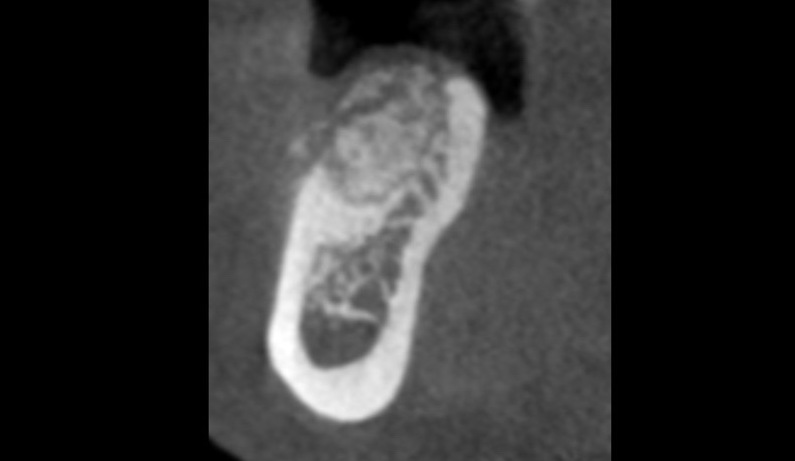

Dental Implant Infection

Case report describing treatment of an infected dental implant from a lesion of endodontic origin involving an adjacent tooth.